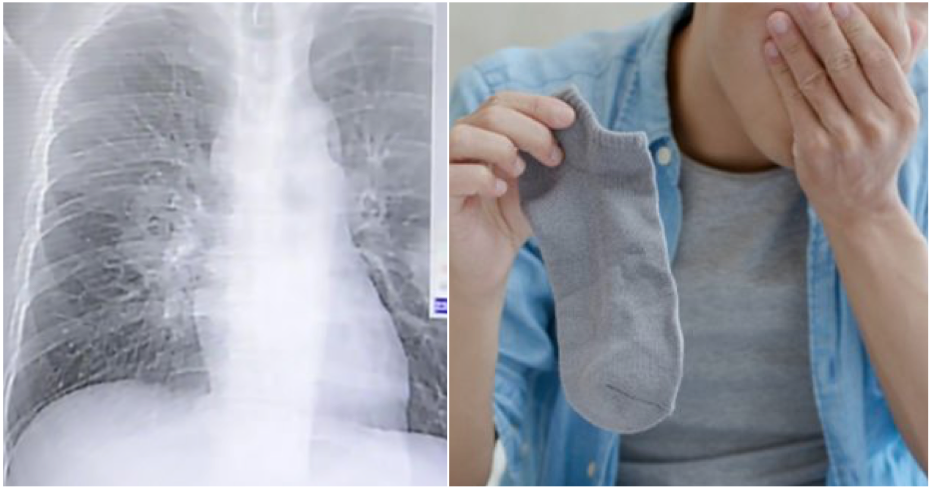

This lack of progress led doctors to conduct further investigations, including X-rays and lung scans. It wasn’t long before they identified a more alarming diagnosis—a fungal infection in the lungs, otherwise known as pulmonary fungal disease.

Fungal infections of the lungs are relatively rare, and they are often seen in individuals with compromised immune systems. While it might have seemed like an unconnected condition at first, further probing by the medical team revealed a possible and highly unusual cause—Peng’s daily sock-sniffing habit.

It turned out that his socks, worn for hours on end, likely contained a buildup of sweat, bacteria, and most crucially, fungal spores. When he sniffed them, he was essentially inhaling these microscopic spores directly into his lungs.

Fungi thrive in dark, damp, and warm environments—socks worn for extended periods provide the perfect breeding ground. As Peng inhaled the spores regularly, it gave the fungus an easy pathway into his respiratory system.